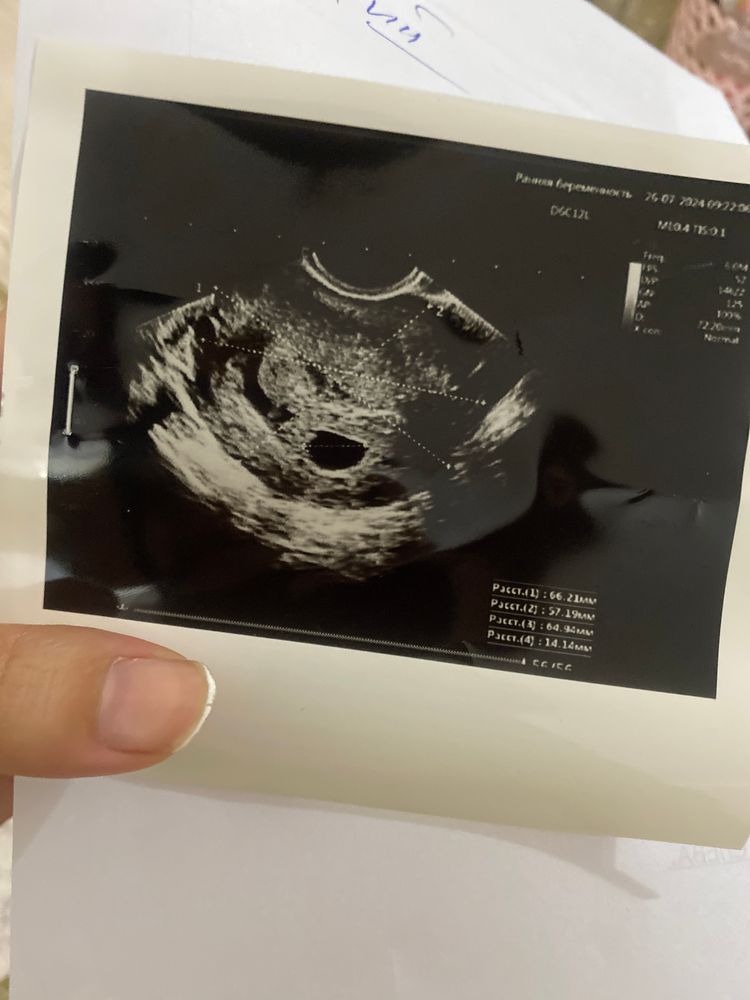

Екатерина Галдина,по узи плодное яйцо растер 29.06 3мм 17.07 10.2мм 26.07 14м

Сабина, странно, что плодное яйцо ещё растёт при таком хгч, хоть и плохо. Короче, гляньте по УЗИ, обычно после зб на малых сроках очень долго можно не ждать. У меня, например, после зб на 9-10 неделях получилось через 4 месяца, но за это время были пайпель-биопсия и корона, поэтому сразу не планировали.